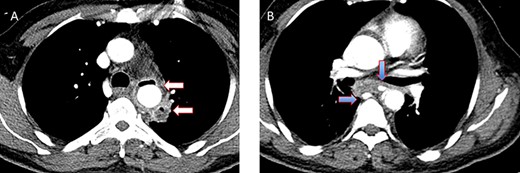

A 36-year-old obese female patient underwent a sleeve gastrectomy abroad. Eleven days after surgery, she presented with an abdominal pain. Abdominal computer tomography (CT) revealed several fluid-air collections (3 abscesses) around the upper greater gastric curve (3.5 × 3.2 cm), lesser sac (7 × 3.3 cm) as well as anterior to the spleen (7 × 3.3 cm). By that time, there was also left pleural effusion and atelectasis of the left lower lung lobe. On the next day, CT-guided aspiration was done (Fig. 1) and a pigtail catheter was inserted to drain the abscesses. On the following day, water-soluble oral contrast displayed an active contrast leak along the proximal sleeve gastrectomy (Fig. 2). On the same day, covered esophageal stent was placed endoscopically. The patient was discharged home and was scheduled for stent removal after 2 weeks. However, after 2 days, the patient presented again with an abdominal pain. The plain x-ray showed slippage of the stent distally. Upper GI endoscopy was done, and the esophageal stent was removed. One day later, the patient condition deteriorated with a massive upper GI bleeding. A CT angiography showed no extravasation and the source of bleeding was not identified during endoscopy due to massive bleeding. An immediately performed angiogram revealed an AEF (Fig. 3). The interventional radiologist achieved transient cessation of the bleeding through embolization of the fistula with interlock coils (Fig. 3). An aortogram showed continuous extravasation of contrast through the fistula, and therefore, endovascular intervention was performed with implantation of 22 mm × 112 mm aortic stent (TEVAR using Valiant covered stent - Medtronic company, USA). One week after TEVAR, another long esophageal stent was positioned (from lower esophagus to the stomach). Two weeks later, a barium swallow proved no evidence of contrast leak. Then, the esophageal stent was removed, and the patient was discharged home. There was a plan for definitive reconstruction procedure, including removal of the endovascular stent and use of reconstructed pericardial bovine graft, however, the patient declined. About 10 months later, she presented with another attack of massive hematemesis, with a drop of hemoglobin to 8 g/dl and a blood pressure of 66/44 mmHg requiring a rapid sequence induction and infusion of packed red blood cells. An immediate abdominal CT showed evidence of peri-stent infection with no contrast extravasation. Upper GI endoscopy showed an evidence of an ischemic ulcer above the Z-line with granulation tissue at the ulcer edge and erosion of the endovascular stent into the lower esophagus. The patient had a positron emission tomography (PET) scan and diagnosed with mediastinitis due to aortic stent infection and septic shock (Fig. 4). Surgical intervention was offered but the patient declined. Treatment with broad spectrum antibiotics and blood transfusion were administrated as required. Around 5 weeks later, the patient developed massive upper GI bleeding requiring intubation and surgical intervention (distal esophagectomy with removal of the endovascular stent and resection and replacement of the AEF site with reconstructed tube using 14 × 9 cm bovine pericardial graft through left thoraco-abdominal incision utilizing left cardiopulmonary bypass and distal perfusion through left femoral artery (Fig. 5). Closure of the stomach with gastrostomy tube insertion for feeding had been performed. One and half year later, reconstruction surgery of the esophagus with colonic interposition was done. After 3-year follow-up, the patient was doing well with no complication.

(A) Aortography showed active contrast extravasation to the esophagus trough the fistula. (B) Coli embolization of the AEF with contrast beyond the coil. (C) Esophagogastroduodenoscopy revealed the site of the fistula and the coil embolization in the stomach. (D) An esophageal stent was placed extending to the stomach and the aortic stent in place. Feeding tube in place.